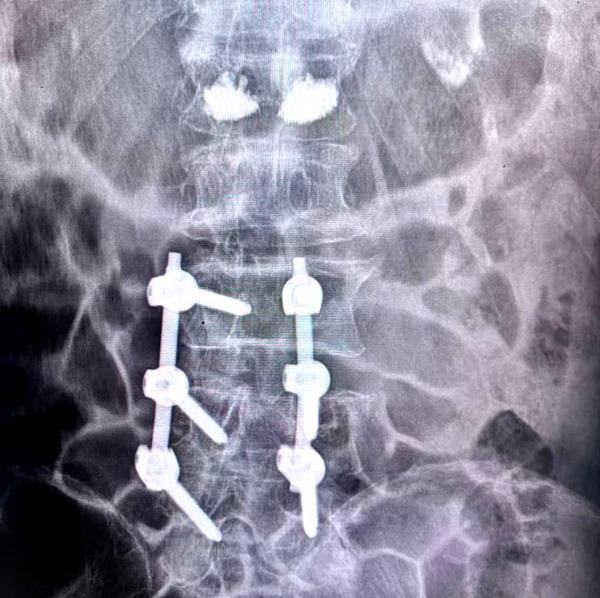

患者经腰1椎体经皮椎体成形术+腰4椎体切开复位钉棒系统内固定术后腰椎部位放射影像

骨科团队经充分讨论后,制定了“微创+开放”的联合手术方案:对腰1椎体采用经皮椎体成形术注入骨水泥强化,快速止痛并稳定椎体;对腰4椎体实施切开复位钉棒系统内固定,重建脊柱稳定性。手术过程顺利,术后患者疼痛明显缓解,脊柱稳定性恢复,目前正逐步康复。